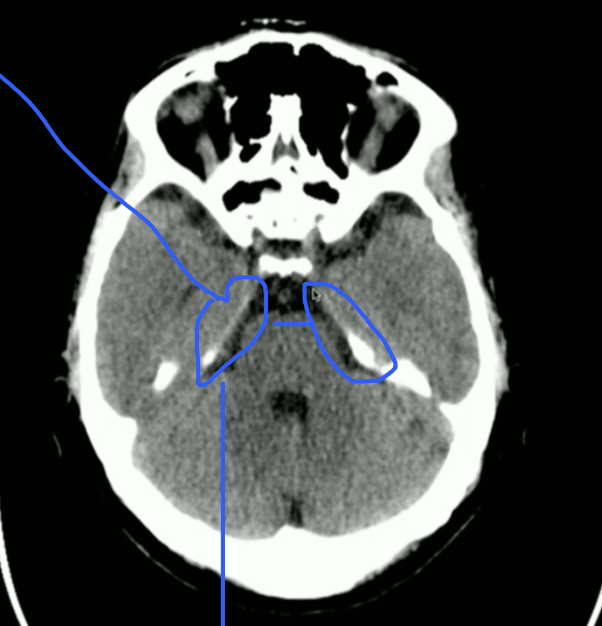

<p>Name these Cisterns</p>

Name these Cisterns

knowt flashcard image